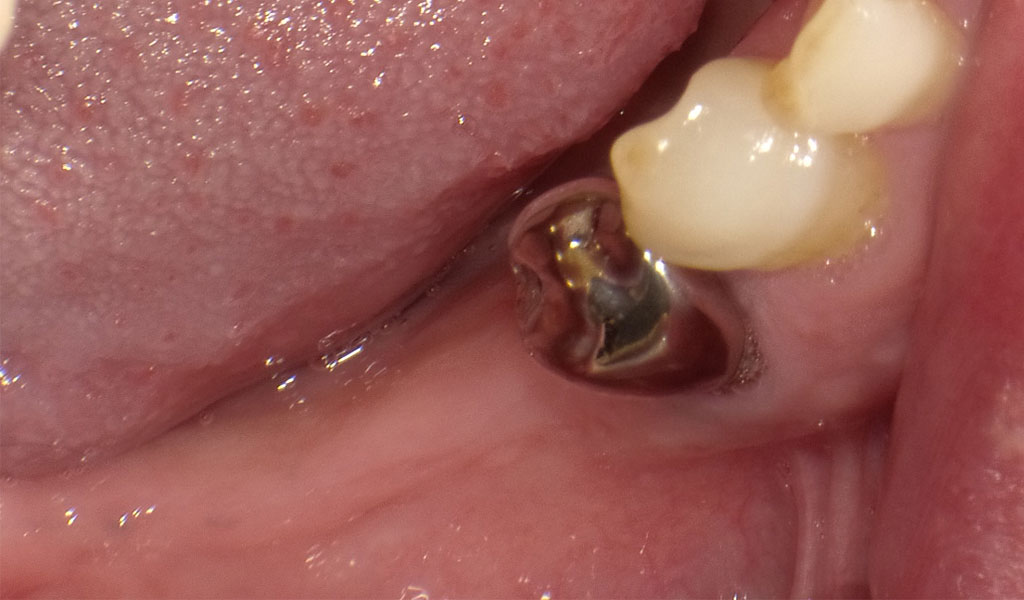

Before1

50代男性・横浜市在住。他院にて右下6,7番を5年前に抜歯済。右下5番がぐらついてきたため、当院を受診。

術前検査(歯周病菌の検査(PCR検査))を行ったところ、Pg菌、Td菌、Tf菌の数値は問題なし。

手術にて、右下5番を抜歯後、右下5番,7番の骨にインプラントを埋め込みました。